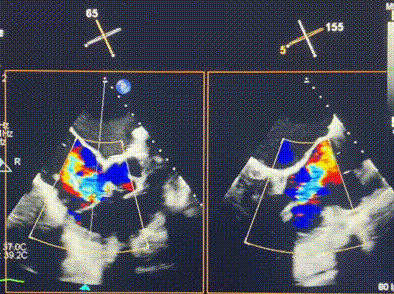

術(shù)后超聲顯示僅殘余微量瓣周漏